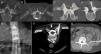

Procedimientos diagnósticos y terapéuticosInfiltracionesLas infiltraciones en columna pueden emplearse de forma diagnóstica o terapéutica. En la figura 3 se exponen algunos ejemplos de infiltraciones.

A y B) En la infiltración foraminal lumbar contactamos con la aguja el disco intervertebral (flecha superior). Para la infiltración facetaria preferimos la parte inferior de la articular inferior, donde contacta con la lámina (flechas inferiores). C) Infiltración facetaria cervical. D) infiltración epidural foraminal a nivel cervical. E) Inyección epidural lumbar interlaminar y facetaria lumbar (F) con control de tomografía computarizada.

Para diagnóstico se inyecta anestésico en el área supuestamente responsable del dolor y se determina si la duración de la analgesia es acorde con el tiempo de acción del anestésico inyectado14. La inyección terapéutica es técnicamente similar, pero al anestésico se le añade glucocorticoide para prolongar el efecto antiinflamatorio sobre la zona dolorosa. Se inyecta un máximo de 20mg de triamcinolona en cada articulación facetaria a tratar, y de 80mg para las infiltraciones epidurales.

Las áreas de actuación suelen ser el disco intervertebral, las estructuras nerviosas y las articulaciones interapofisarias. La inyección intradiscal de glucocorticoides puede estar indicada en pacientes con dolor de origen discógeno y puede realizarse en el mismo procedimiento de la discografía, cuando resulta positiva. Aunque es un procedimiento controvertido, algunos autores lo consideran eficaz para el alivio temporal de los síntomas cuando existen signos de degeneración discal con edema óseo vertebral subcondral (cambios Modic tipo i)15.

En el caso de las estructuras nerviosas se infiltra el espacio epidural y/o perirradicular. La aproximación epidural se puede hacer por vía caudal, transforaminal o interlaminar. Suele estar indicada en pacientes con radiculopatía y que no han respondido de forma satisfactoria al tratamiento conservador. En el dolor espinal no referido se deben considerar otras técnicas.

Se considera que las inyecciones transforaminales son más eficaces que las interlaminares debido a la deposición de mayor cantidad de medicación en el espacio epidural anterior16, aunque del análisis de revisiones sistemáticas se concluyó que, a nivel lumbar, la inyección caudal de corticoides es la forma más efectiva de infiltración epidural17.

La seguridad de las inyecciones epidurales cervicales transforaminales se ha cuestionado debido a la presentación de complicaciones graves como infarto cerebral, medular y muerte, por lo que han sido abandonadas en muchos hospitales18. Estas complicaciones pueden ser secundarias a vasoespasmo, embolia por partículas de glucocorticoides o lesión directa de una arteria radicular. A nivel lumbar, aunque más raro, también se han comunicado complicaciones similares tras la infiltración transforaminal19. Especial precaución debe de tenerse en las inyecciones altas, ya que la más grande de las arterias radiculares, la arteria de Adamkiewicz, se origina entre T9 y T12 en el 75% de los casos, y entre L1 y L2 en un 10%, aunque puede tener un origen tan alto como T520. Como medidas preventivas se ha recomendado el uso de glucocorticoides solubles, para disminuir el riesgo de embolia por partículas, y de agujas de punta roma, que minimicen el riesgo de lesión vascular. Un estudio reciente no ha demostrado diferencias significativas en la reducción del dolor en las infiltraciones cervicales con el uso de glucocorticoides solubles frente a los insolubles21.

Las articulaciones facetarias se consideran responsables del dolor cervical crónico en el 36-67% de los casos, diagnosticado mediante infiltración anestésica guiada por imagen. La distribución de los fármacos, intraarticular o periarticular, no influye en el porcentaje de alivio del dolor22.

Sobre las infiltraciones facetarias dorsales se ha publicado poco, pero también se consideran útiles cuando el diagnóstico es apropiado23.

A nivel lumbar las facetas articulares se consideran responsables del dolor crónico en el 15-45% de los pacientes con lumbalgia crónica. Los resultados del tratamiento son inferiores en las infiltraciones intraarticulares frente al bloqueo del ramo dorsal que inerva las facetas4,24. Tampoco se han encontrado diferencias significativas entre la infiltración con anestésico aislado o asociado a glucocorticoides25.

En ocasiones la degeneración facetaria viene asociada a la presencia de quistes sinoviales o gangliones paravertebrales. Pueden ser sintomáticos por su tamaño o por compresión de estructuras nerviosas vecinas. De forma percutánea se puede aspirar su contenido, que, como suele ser gelatinoso, requiere una aguja de mayor calibre (14G). Tras el drenaje se infiltra con glucocorticoides y/o anestésico26.

Las articulaciones sacroilíacas se consideran responsables de lumbalgia crónica en el 10-19% de los casos. La evidencia de la utilidad de las infiltraciones como técnica diagnóstica es superior a su uso como método terapéutico27. El efecto terapéutico suele ser mayor en pacientes sin fusión articular28 y cuando se hace infiltración conjunta intraarticular y extraarticular29.